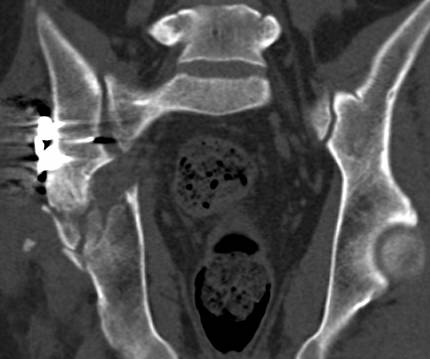

[Ortho] перелом правой половины таза

высылаю дополнительно  сканы.